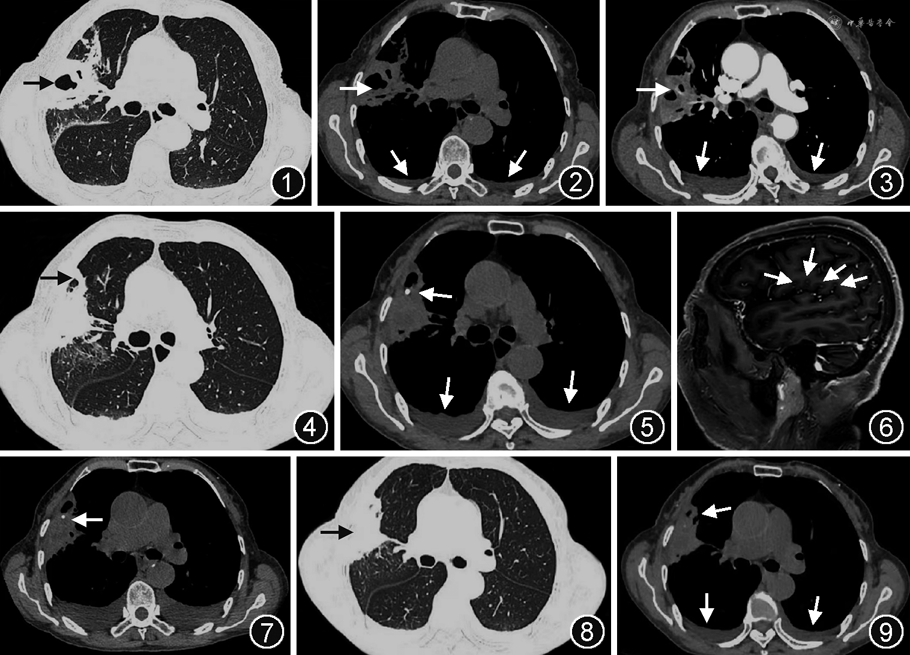

患者女,78岁,农民,因“发热4 d”于2022年2月20日门诊收入院。患者4 d前无明显诱因出现发热,体温最高39.3 ℃,无畏寒、寒战,伴食欲差、恶心,无呕吐,2022年2月18日当地医院给予抗感染、退热等治疗(具体不详),患者仍反复发热,伴乏力。于我院门诊行胸部CT检查可见右肺上叶后段见空洞性病变、胸腔积液等(图1,2)。既往有“高血压病”10年余,平素使用降压药物(具体不详),血压控制可;“脑梗死”1年,未遗留后遗症;“血糖升高”2 d。个人史等无特殊。入院体检:体温38.0 ℃、脉率79次/min、呼吸频率20次/min、血压160/73 mmHg(1 mmHg=0.133 kPa)。浅表淋巴结未触及肿大,咽部无充血、扁桃体无肿大,双肺呼吸音粗、双肺未闻及啰音。实验室检查:新型冠状病毒核酸测定阴性;血气分析(未吸氧):pH值7.45,二氧化碳分压35 mmHg,氧分压92 mmHg;血钾2.91 mmol/L;空腹血糖4.92 mmol/L,糖化血红蛋白6.5%;血常规:中性粒细胞百分比(N%)80.10%,中性粒细胞计数(NEU)6.74×109/L,淋巴细胞百分比(Lym%)10.20%,淋巴细胞计数(Lym)0.86×109/L,余未见异常;C反应蛋白(CRP)24.19 mg/L,血清淀粉样蛋白A(SAA)93.44 mg/L,降钙素原0.367 μg/L,ESR为39.00 mm/1 h,IL-6为51.6 ng/L,铁蛋白783.97 μg/L;B型钠尿肽314 ng/L,D-二聚体1.50 mg/L;肝功能:总蛋白68 g/L,白蛋白42 g/L,均在正常参考值范围内。入院初步诊断“右肺空洞性质待定:肺脓肿?肺癌?胸腔积液、电解质紊乱(低钾血症)、高血压病、陈旧性脑梗死”,给予哌拉西林(4.5 g,1次/8 h)联合莫西沙星(0.4 g,1次/d)抗感染等治疗。为明确病灶性质于2022年2月21日行胸部增强CT检查,可见右肺上叶空洞性病变并均匀强化,符合感染性病变并脓肿形成(图3),患者及家属拒绝行支气管镜检查进一步明确病变性质,遂调整为亚胺培南(1 g,1次/8 h)加强抗感染;2月24日尿常规示酵母菌101.40/μl,加用氟康唑(0.2 g,1次/d,静脉滴注)抗真菌;行曲霉血清学试验、真菌D-葡聚糖检测、血培养(5 d)鉴定及药敏、风湿及免疫相关抗体、结核杆菌抗体、肿瘤标志物等均未见异常。因患者仍间断发热,考虑肺脓肿革兰阳性球菌感染风险大,为提高肺内药物浓度,加用利奈唑胺(0.6 g,1次/12 h)覆盖金黄色葡萄球菌、链球菌及MRSA等。

2022年2月27日患者出现神志恍惚、谵妄,急查血气(吸氧浓度33%)示pH值7.56,二氧化碳分压30 mmHg,总二氧化碳分压27.80 mmHg,剩余碱4.7 mmol/L,标准碳酸氢盐29.00 mmol/L,钠111.00 mmol/L、氯78 mmol/L,患者呼吸性碱中毒合并代谢性碱中毒,考虑摄入不足及感染消耗所致低钠低氯血症并出现意识状态改变;治疗后复查血常规:N%为67.60%,NEU为3.48×109/L,Lym%为22.80%,Lym为1.67×109/L,淋巴细胞恢复正常;胸部CT可见右肺上叶空洞性病变较前缩小(图4,5),颅脑MRI及增强可见脑内多发斑点状、小结节状异常强化影(图6),感染性病变与转移瘤待鉴别,因家属拒绝创伤性检查,且亚胺培南难于透过血脑屏障,遂调整为美罗培南(1 g,1次/8 h)继续抗感染,行PET-CT检查见右肺上叶高密度影并FDG代谢增高(图7)、脑内异常FDG代谢增高灶、右侧侧脑室后角局限显示欠清并FDG代谢增高,均考虑感染所致;双肾FDG代谢欠均匀,不除外感染。至此,考虑患者存在肺脓肿、颅脑感染、尿路感染,但致病菌不明确。为明确致病菌行腰椎穿刺术,并留取脑脊液送基因二代测序(next generation sequencing,NGS)。3月11日脑脊液NGS结果回示诺卡菌属(序列数7),豚鼠耳炎诺卡菌(序列数6)。根据PET-CT检查及脑脊液NGS结果,患者豚鼠耳炎诺卡菌病血流感染诊断明确,已播散至肺、脑、肾多部位,加用足量磺胺甲噁唑/甲氧苄啶(SMZ,2.4 g,1次/6 h)治疗。患者治疗后复查血常规、电解质、肝肾功能均未见异常;胸部及输尿管全程CT示右肺上叶空洞性病变较前略减小(图8,9);输尿管全程未见异常。于2022年3月16日好转出院,出院后继续口服利奈唑胺和SMZ治疗。4月28日患者胸部CT示右肺上叶空洞性病变明显减小;自6月4日停用利奈唑胺,口服SMZ(0.96 g,1次/6 h)维持治疗6个月,出院6个月及1年后电话随访,患者一般情况良好,病情未复发。

诺卡菌感染以化脓性炎症为主,可形成急性化脓性肺炎、孤立的肺脓肿或散在的粟粒样浸润,慢性病灶表现为进行性纤维化样改变,甚至合并肉芽肿改变[8]。所以,诺卡菌感染影像学以结节影、斑片渗出、实变影多见,其内可有液化或坏死,也可形成空洞,引起周围播散,导致胸膜增厚、脓胸或直接侵犯胸壁[9, 10, 11, 12, 13]。本例患者胸部CT右肺上叶病灶呈片状实变,内见空气支气管相及含气空洞影;增强CT示病灶均匀强化,中心液性密度未见强化,双侧胸膜局限增厚等无特异性影像表现,因此早期诊断困难,需与侵袭性真菌病、肺结核、肺癌、肉芽肿性血管炎等疾病进行鉴别。